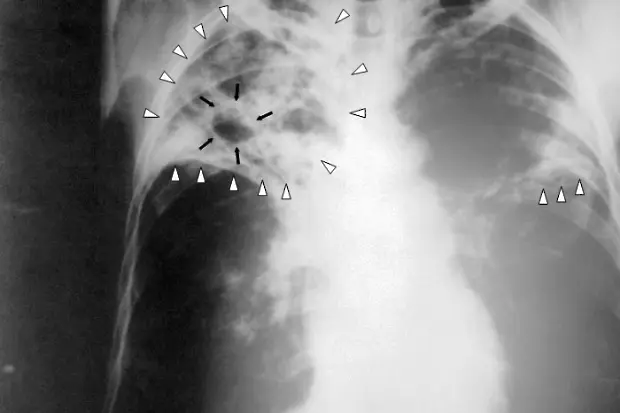

Пневмонията е възпалително заболяване на белите дробове, при което се нарушава нормалния процес на дишане. Тя винаги трябва да се счита за сериозно заболяване, независимо че при наличие на мощни антибактериални средства, най-често се изкарва "на крак". В зависимост от защитните сили на организма, придружаващите заболявания и възрастта тежестта на протичане варира от почти безсимптомни форми, до тежка дихателна недостатъчност с опасност за живота на болния.